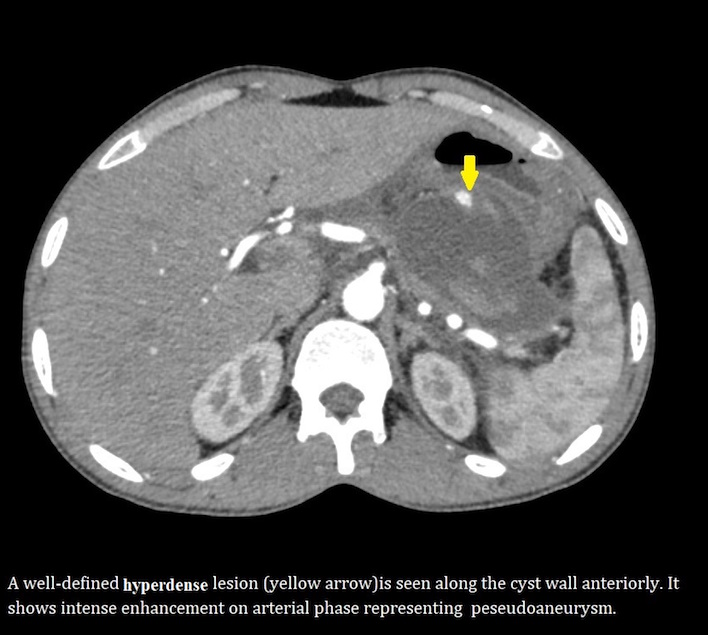

A well-defined oval cyst isseen abutting the pancreatic body and tail, suggestive of a pancreatic pseudocyst. The pancreatic duct is minimally prominent. Thecyst is seen anteriorly abutting the stomach wall with resultant diffuse oedematousthickening of the walls of the stomach.A few ill-defined hyperdensitiesare seen within the cyst, suggestive of chronic hemorrhages/ sludge •Atiny nodular well-defined intensely enhancing lesion is seen along the cyst wall anteriorly on arterialphase representing peseudoaneurysm.

- High-resolution MDCT or MR angiography can depict the pseudoaneurysm as a well-delineated rounded structure originating from the donor artery.